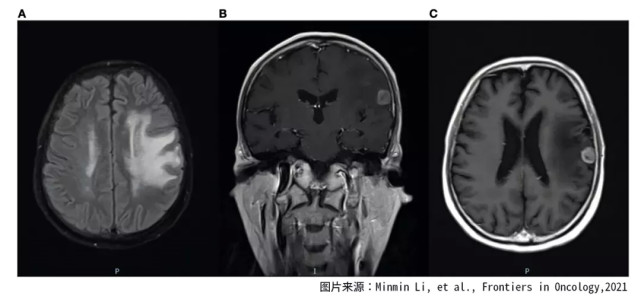

2016年1月,时隔近五年,患者出现了病情进展的迹象。医生使用18毫米准直器对患者的脑单病灶进行了放疗,放疗靶区中心剂量为25.4格瑞,治疗评估为部分缓解。但是3个月之后,出现了新的脑部病灶。由于放疗后短时间内复发,因此选择了尼莫司汀化疗,治疗时间为四周,作为姑息治疗方式。由于后期反复的肺部感染严重影响了患者的健康, 患者于2018年8月不幸因呼吸衰竭而去世。

图片图3.2016年4月放疗之后再次出现脑进展

尽管在治疗期间进行了多次放射治疗,但是患者的生活质量良好,即使进行了二次全脑放射治疗,也没有出现严重的神经认知缺陷和其他严重的不良反应。